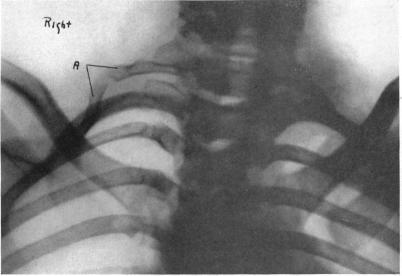

CERVICAL RIB: A METHOD OF ANTERIOR APPROACH FOR RELIEF OF SYMPTOMS BY DIVISION OF THE SCALENUS ANTICUS.

Ann Surg. 1927 Jun;85(6):839-57. doi: 10.1097/00000658-192785060-00005.

II. Cervical Ribs.

Ann Surg. 1901 Nov;34(5):637-48. doi: 10.1097/00000658-190107000-00067.